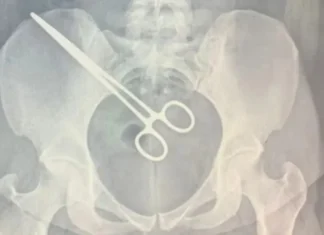

Mulher descobre pinça dentro do corpo em visita na cadeia

A Santa Casa de Araçatuba, localizada no interior de São Paulo, está investigando a conduta de médicos após a descoberta de uma pinça esquecida...